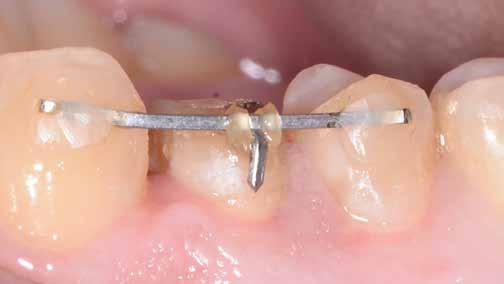

4. ábra: A fogszerkezet helyreállítása és a fogrestaurációs komplexum ellenálló képességének javítása érdekében ortodontikus extrúziót végeztek a szomszédos fogakra ragasztott drót és egy egyszerű rugalmas ligatúra segítségével.

5. ábra: Az extrudálás nyomon követése néhány hét múlva. Az extrúzió végén a lágyrészek kisebb mértékű újrakontúrozása történt. A szerző általában fibrectomia nélkül végzi az extrúziót, és az extrúzió végén a lágyrészek újrakontúrozását végzi.

6. ábra: A fog az extrúzió és a függőleges preparálás után. A függőleges preparáció a legjobb preparátum a fog szerkezetének megőrzése szempontjából, különösen akkor, ha minimálisan invazív megközelítéssel alkalmazzák. A szerző egy módosított vertikális technikát alkalmaz, amely nagyobb hangsúlyt fektet a pericervikális dentin fenntartására.

7. ábra: A bukkális szerkezet összehasonlítása extrudálás előtt/után . A maradék fogazati struktúra okklusális terhelése most sokkal kedvezőbb a hosszú távú eredmény szempontjából .